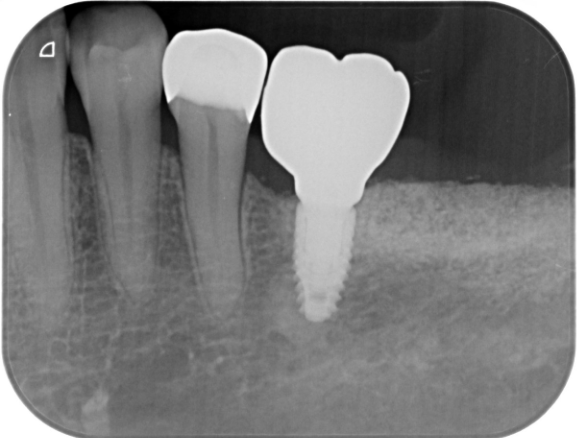

症例3

| 通院期間 | 9か月 |

| 来院回数 | 12回 |

| 治療費 | 総額:835,000円(税抜) 【内訳】 インプラント埋入手術250,000円、GBR(骨再生手術)150,000円、2次手術+FGG(遊離歯肉移植術)55,000+60,000円、仮歯30,000円、インプラント上部構造(セラミッククラウン)170,000円、隣在歯セラミッククラウンのやりかえ120,000円 |

| リスクと副作用 | 定期的なメンテナンスが必要、術後若干の腫れと痛み |

| ここがこだわりのポイント!☝ | インプラント周囲に角化歯肉と言われる健常な歯肉がなかったので、口蓋からの歯肉移植を行っています💡この角化歯肉がないと、インプラントをしてもうまく歯磨きができないことがあります。 |